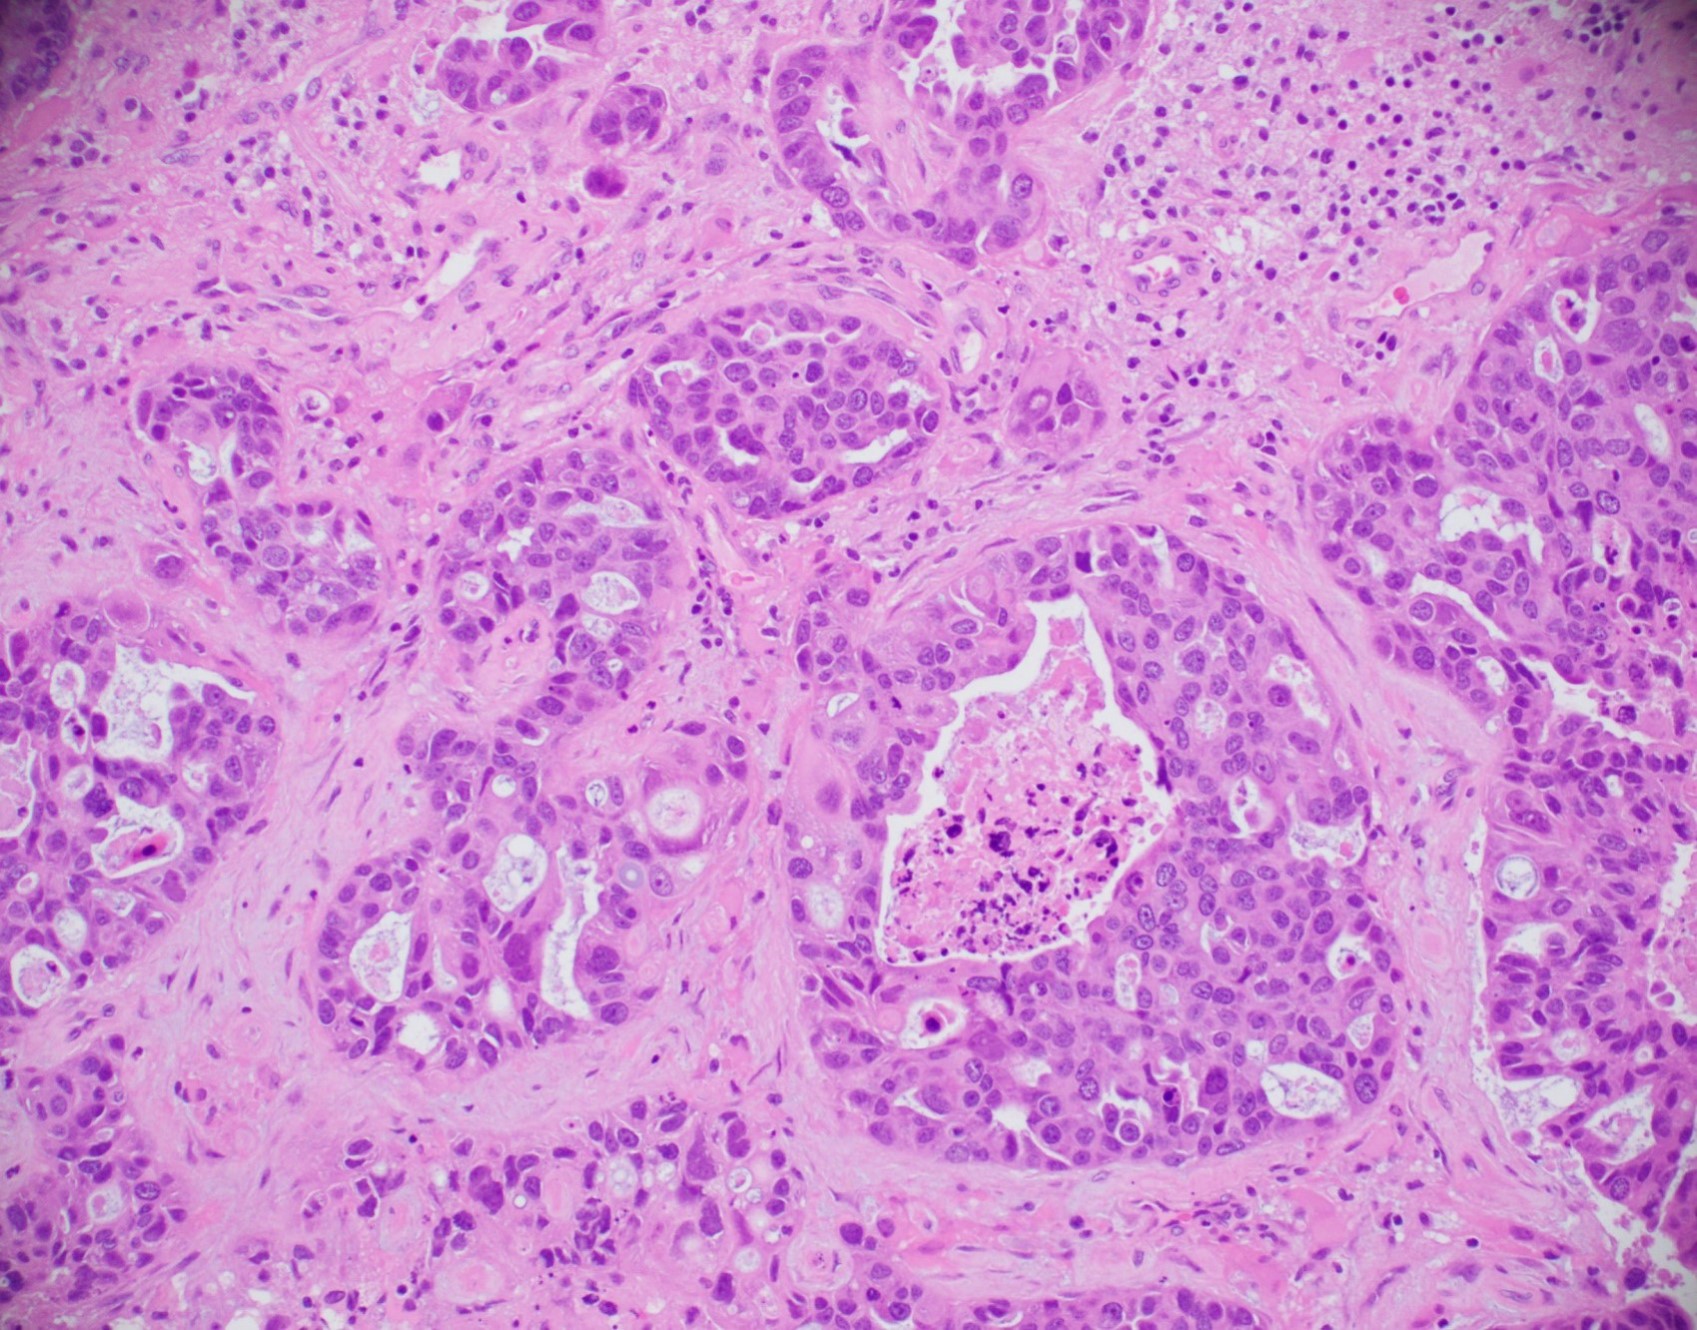

Microscopic (histologic) description

- Histologic grading is based on the Nottingham / modified Bloom & Richardson Score (Histopathology 1991;19:403):

- Tubule formation (1 - 3 points):

- > 75% (1 point)

- 10 - 75% (2 points)

- < 10% (3 points)

- Nuclear pleomorphism (1 - 3 points):

- Small, regular, uniform, similar to normal ductal epithelial cells, 2 - 3x RBC (1 point)

- Moderate increase in size / variability (2 points)

- Large nuclei, marked variation, often vesicular chromatin with prominent nucleoli (3 points)

- Mitotic count (1 - 3 points), dependent on microscopic field area

- Total score (add points for tubule formation, nuclear pleomorphism and mitotic count):

- 3 - 5 points: grade 1

- 6 - 7 points: grade 2

- 8 - 9 points: grade 3

- Histological features of IBC NST vary considerably from case to case and even within the same case

- Margins vary from highly infiltrative, permeating the surrounding tissue, to continuous pushing margins

- Architecture varies from sheets, nests, clusters, cords or individual cells (but lacks the cytomorphological characteristics of invasive lobular carcinoma)

- Tubular formations are prominent in well differentiated tumors but absent in poorly differentiated tumors

- Variable cytological features:

- Cytoplasm may be abundant and eosinophilic but it can show other features in some tumors, including as clear, foamy or granular

- Nuclei may be regular and uniform or highly pleomorphic with prominent or multiple nucleoli

- Mitotic figures are variable from virtually absent to extensive

- 2 distinct growth patterns exist:

- Large and solid nests or syncytial infiltrative growth pattern with little associated stroma and an expansive growth that compresses the surrounding stroma (e.g., most basal-like breast cancers)

- Tumors characterized by small cancer nests accompanied by marked fibrosis (desmoplastic / scirrhous); this type diffusely infiltrates the surrounding tissue as an irregular shaped spiculated mass

- Calcification in 60% of cases, variable necrosis

- Elastosis involves stroma, wall of vessels and ducts and causes grossly noted chalky streaks

- Often ductal carcinoma in situ (DCIS) (up to 80%)

- In some cases, DCIS is extensive

- Associated DCIS is usually of same nuclear grade as the invasive carcinoma

- Perineural invasion (28%)

- Mast cells are associated with low grade tumors

- Uncommon features: eosinophils intraluminal crystalloids (BMC Cancer 2007;7:165, Arch Pathol Lab Med 1997;121:593)

- No myoepithelial cell lining (as seen in DCIS or benign lesions)

- Angiolymphatic invasion in 35%; differs from tissue retraction because:

- Occurs outside margin of carcinoma

- Does not conform precisely to space it is in

- Endothelial lining is present and is CD31+, ERG, D2-40+, CD34+ and factor VIII+

Microscopic (histologic) images

Contributed by Julie M. Jorns, M.D., Kristen E. Muller, D.O., Gary Tozbikian, M.D. and Emad Rakha, M.D.